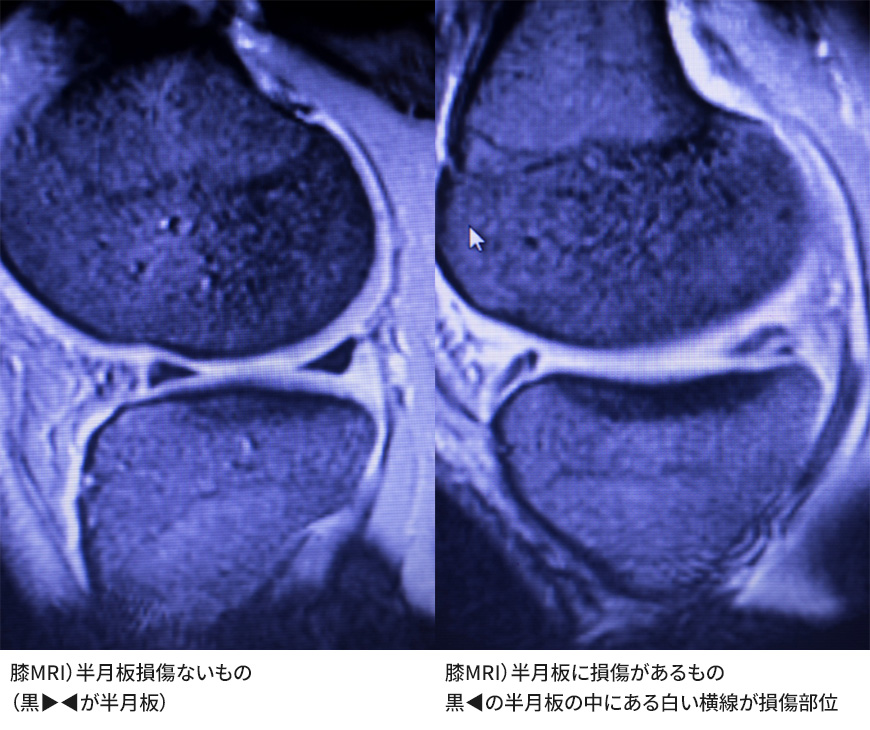

半月板損傷

半月板損傷はスポーツや交通事故で受傷することが多く、自然治癒しにくい障害です。半月板の外周1/3にしか血流がなく、適切な治療をしないと変形性膝関節症のリスクが高まります。

損傷には、外傷によるものと、加齢で変性し軽微な外力で悪化する変性断裂があります。生まれつき半月板が分厚い円板状半月も原因となります。特に内側半月板が損傷しやすく、膝を深く曲げたり捻ると内側後方に痛みが出やすくなります。

膝の曲げ伸ばしで引っかかり感があり、炎症による水腫で腫れることもあります。悪化すると「ロッキング」が起こり、膝が動かなくなり歩行困難となることがあります。

MRIは、靭帯・半月板・骨髄浮腫・軟骨障害を詳細に確認できます。ベーカー嚢腫の評価や正常画像との比較で病状を説明しやすくなります。